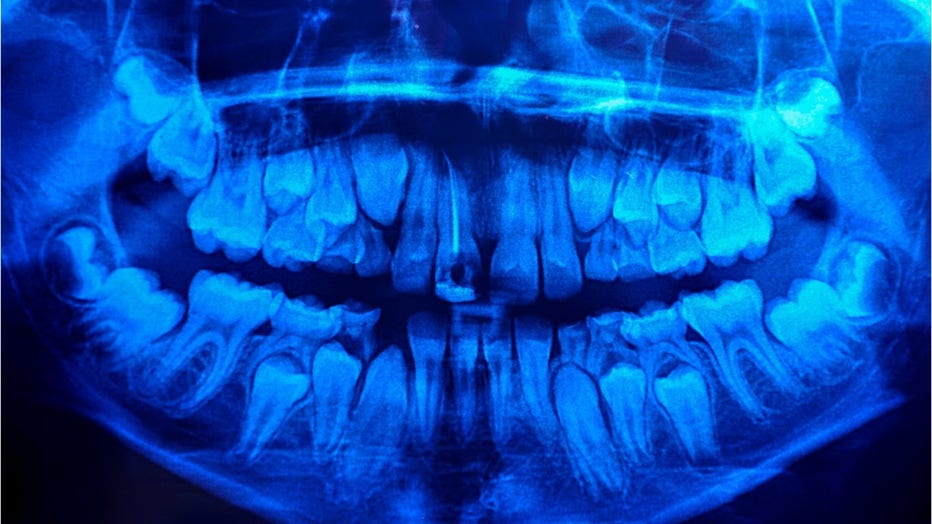

Odontomas are benign tumors composed of dental tissue, but the majority of cases are asymptomatic and only identified thought X-ray. It’s typically slow-growing and is the most common odontogenic tumor found in the jaw, but the cause is relatively unknown, according to a 2014 National Institutes of Health case report.